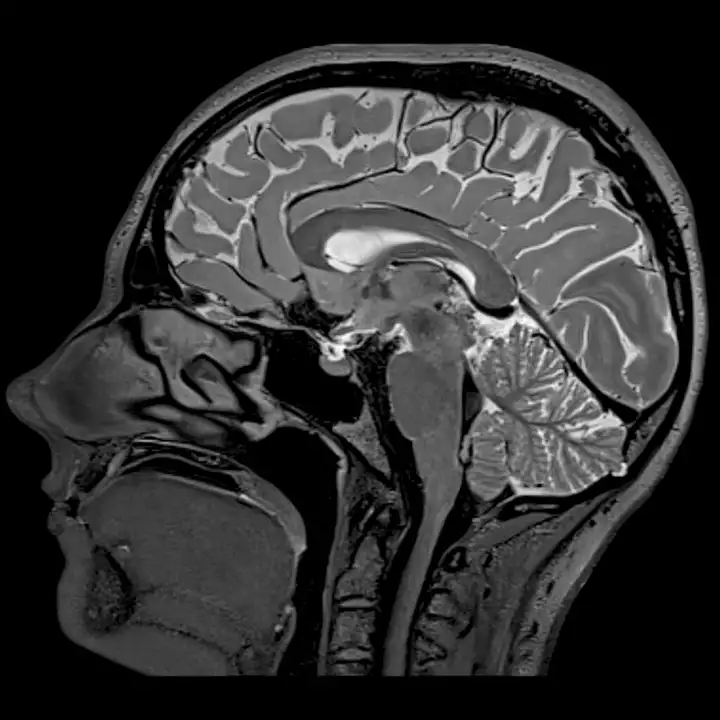

В старых постах я уже опровергла миф о том, что интеллект зависит от соотношения размеров мозга и тела. Расстояние между нейронами возрастает вместе с размерами тела только у млекопитающих. Так у бурого медведя( brown bear) в коре больших полушарий примерно столько же нейронов, сколько у кошки(cat)

Еще один пример - мозг слона. Он больше человеческого. Весит он 4 - 5 кг, когда наш - всего полтора. Тем не менее, слоны обладают лишь интеллектом ребенка. Это легко объяснить тем, что из-за большого размера у слона в передних полушариях не так плотно, как у нас, расположены нейроны. У слона там всего 5 миллиардов нейронов, в то время как у человека в полушариях 16-21 миллиард (во всем мозге 86). Получается, главный показатель интеллекта - количество нейронов?

Так получается, колличество нейронов не важно? Тогда что важно? Организация мозга. Совершенный мозг делится на зоны, каждая из которых специализируется на своей роли. Мозг со специализированными зонами - как команда со профессиональными сотрудниками. Она будет работать эффективнее обычной группы людей даже если профессионалов(нейронов) меньше.